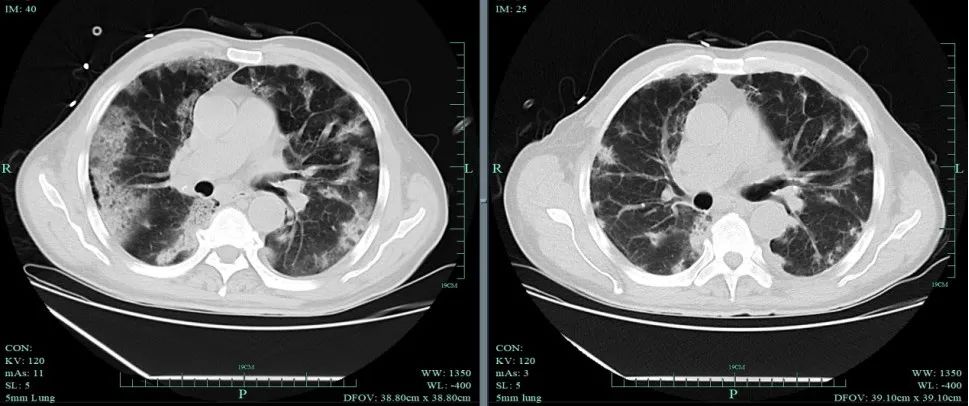

在當(dāng)?shù)蒯t(yī)院,李叔先檢查了血常規(guī),白細(xì)胞指數(shù)已經(jīng)達(dá)到了正常值的6倍多,中性粒細(xì)胞細(xì)胞指數(shù)超過(guò)正常值十多倍,呼吸道病原體核酸檢測(cè)為甲型流感病毒陽(yáng)性,胸部CT平掃考慮兩肺多發(fā)感染。

在浙大一院感染病科盛吉芳主任醫(yī)師門(mén)診,李叔呼吸急促,專家拿聽(tīng)診器仔細(xì)聽(tīng)后發(fā)現(xiàn)——雙肺存在濕啰音,結(jié)合兩肺多發(fā)斑片狀高密度影的肺部CT報(bào)告,不禁皺起眉頭。

“肺都白了這么多,屬于比較典型的重癥肺炎,需要住院治療”,鑒于李叔病情較重,盛吉芳主任醫(yī)師當(dāng)即建議他先吸氧緩解呼吸困難,而后經(jīng)過(guò)醫(yī)護(hù)人員的抗病毒、抗炎以及對(duì)癥治療,肺炎才被阻擊。

住院不到一周,李叔的肺炎明顯好轉(zhuǎn),氣管腔內(nèi)的痰液也減少了。“治療效果不錯(cuò),過(guò)兩天就可以出院了”,查房的時(shí)候,盛吉芳主任醫(yī)師笑著說(shuō)。